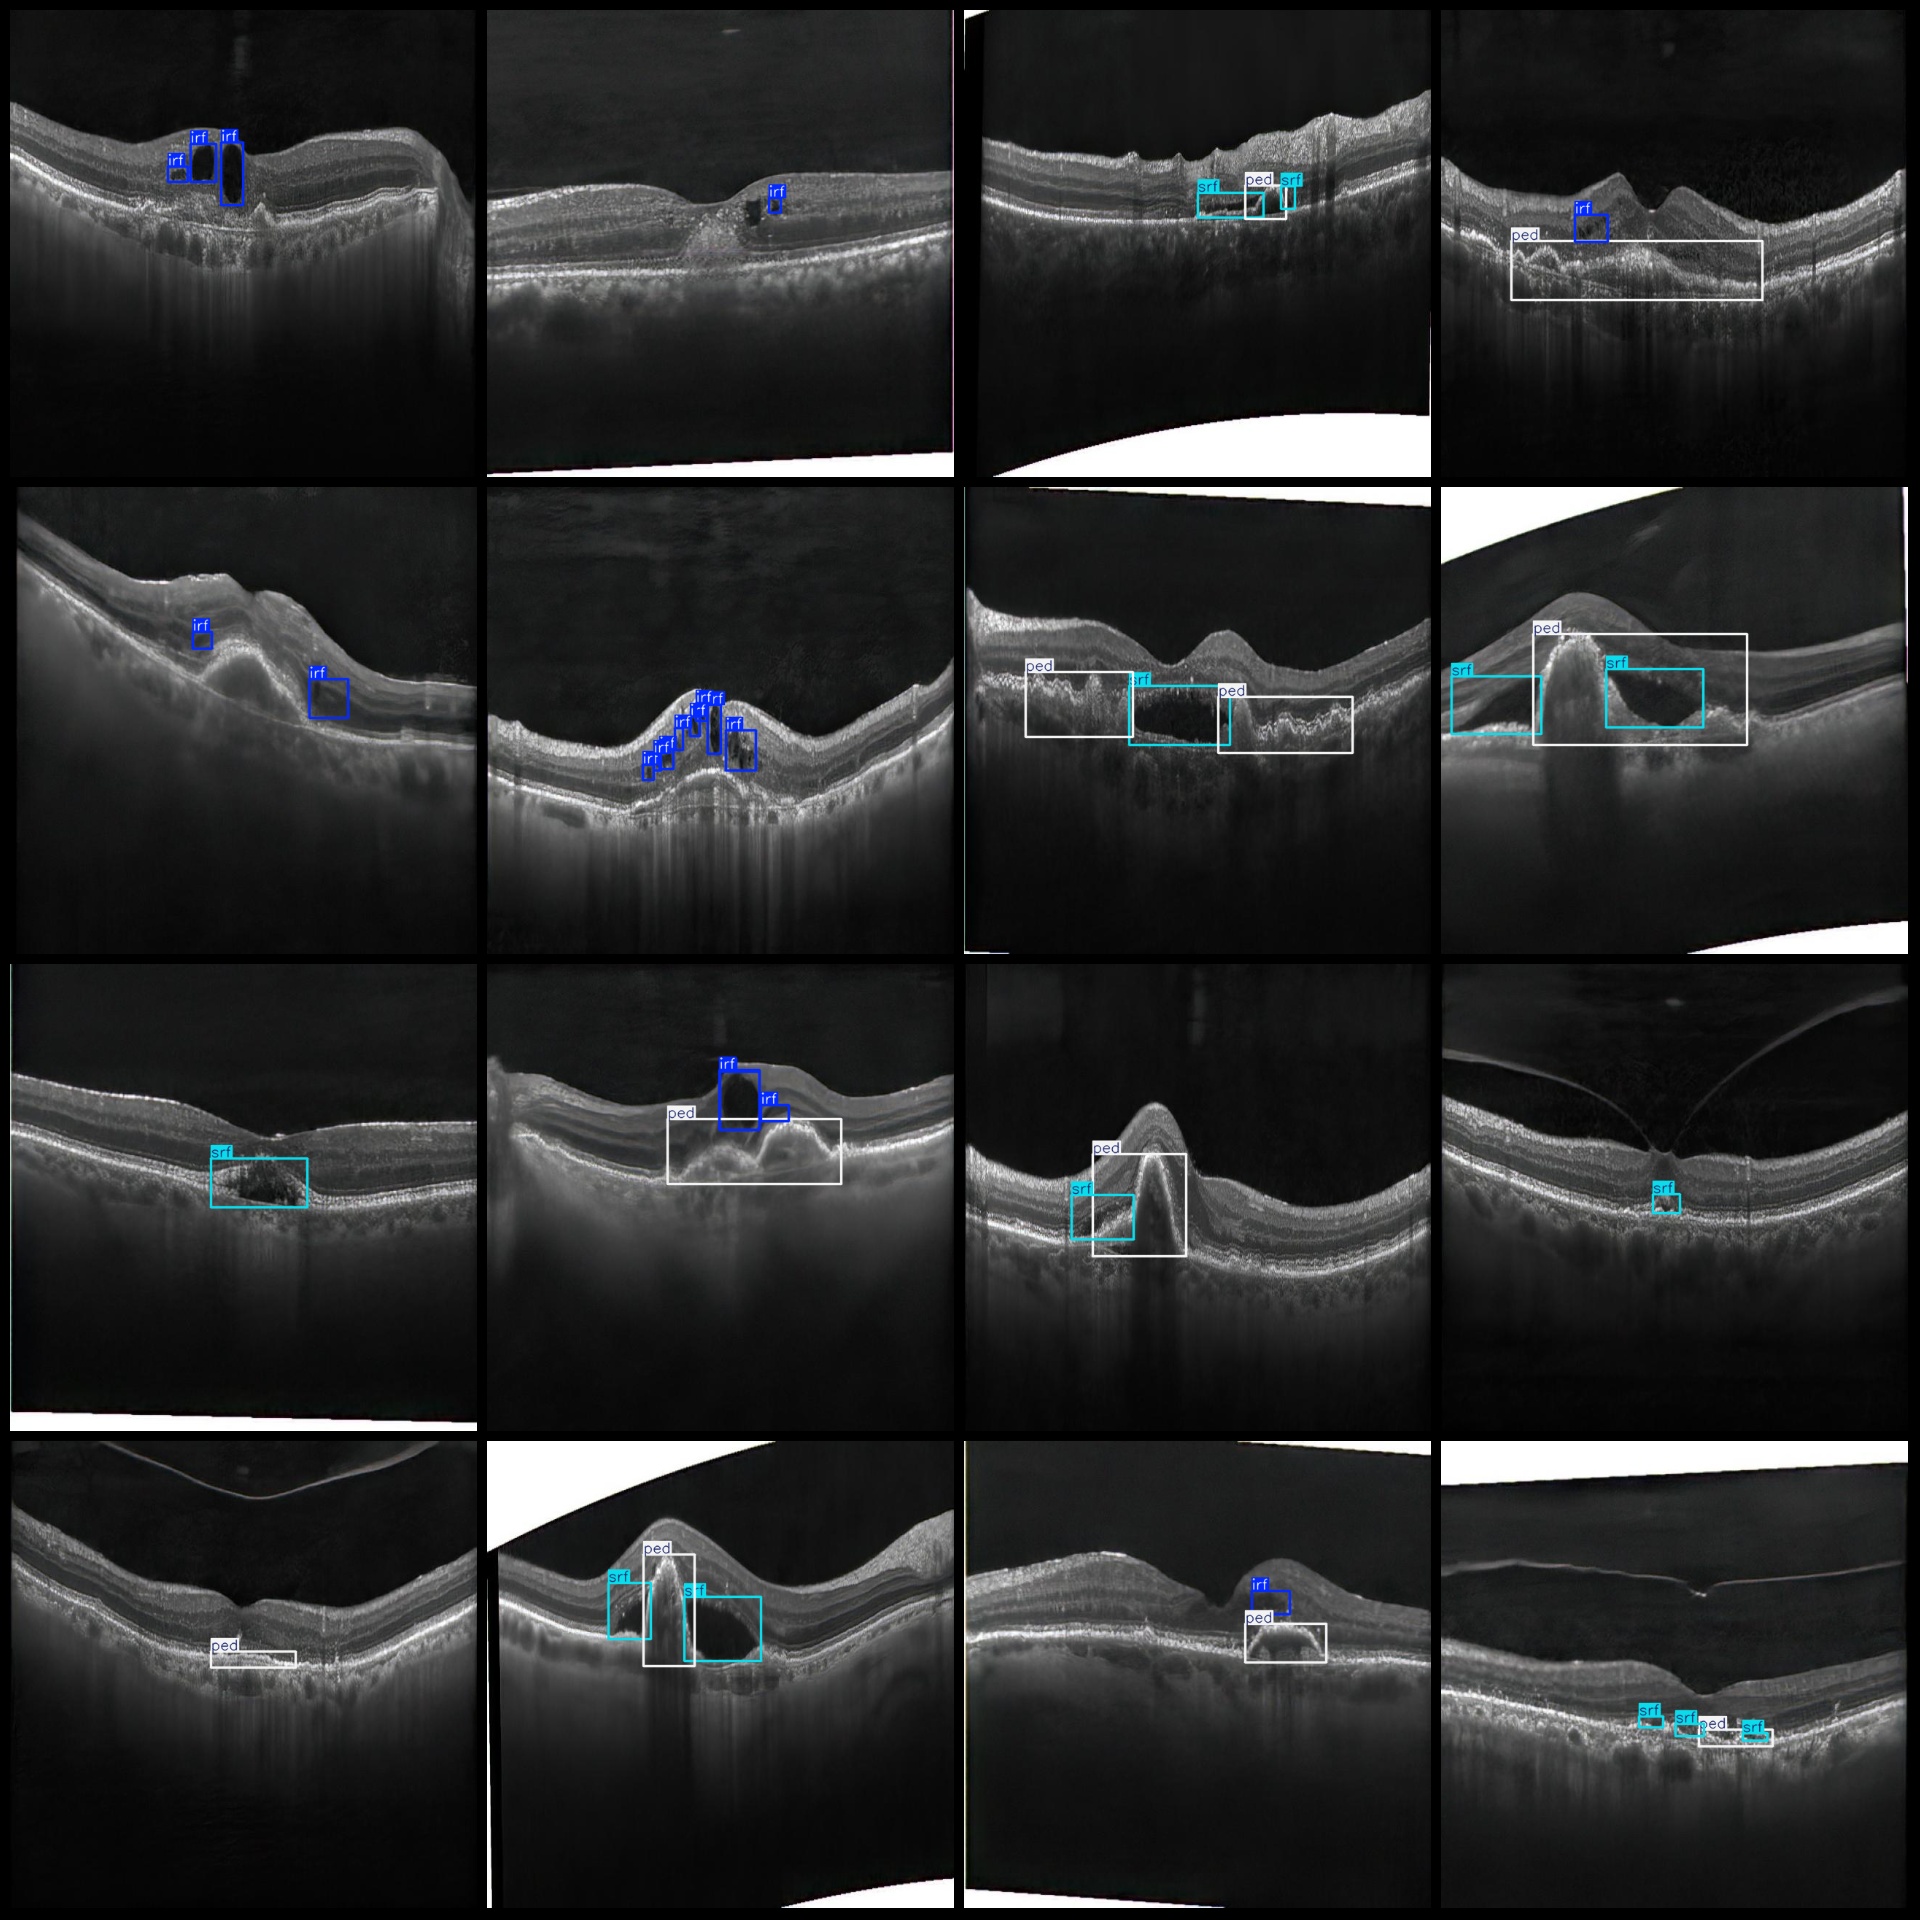

图片预览:

标注例子:

标注类别名称(注意yolo格式类别顺序不和这个对应,而以labels文件夹classes.txt为准):["irf","organized_subretinal_scar","ped","srf","subretinal_hyperreflective_material","virteliform_lesion"]

irf(视网膜内高反射点) 框数 = 4878

organized_subretinal_scar(组织化视网膜下瘢痕) 框数 = 326

ped(色素上皮脱离) 框数 = 3611

srf(视网膜下液) 框数 = 3794

subretinal_hyperreflective_material(视网膜下高反射物质) 框数 = 91

virteliform_lesion(玻璃膜疣样病变) 框数 = 194